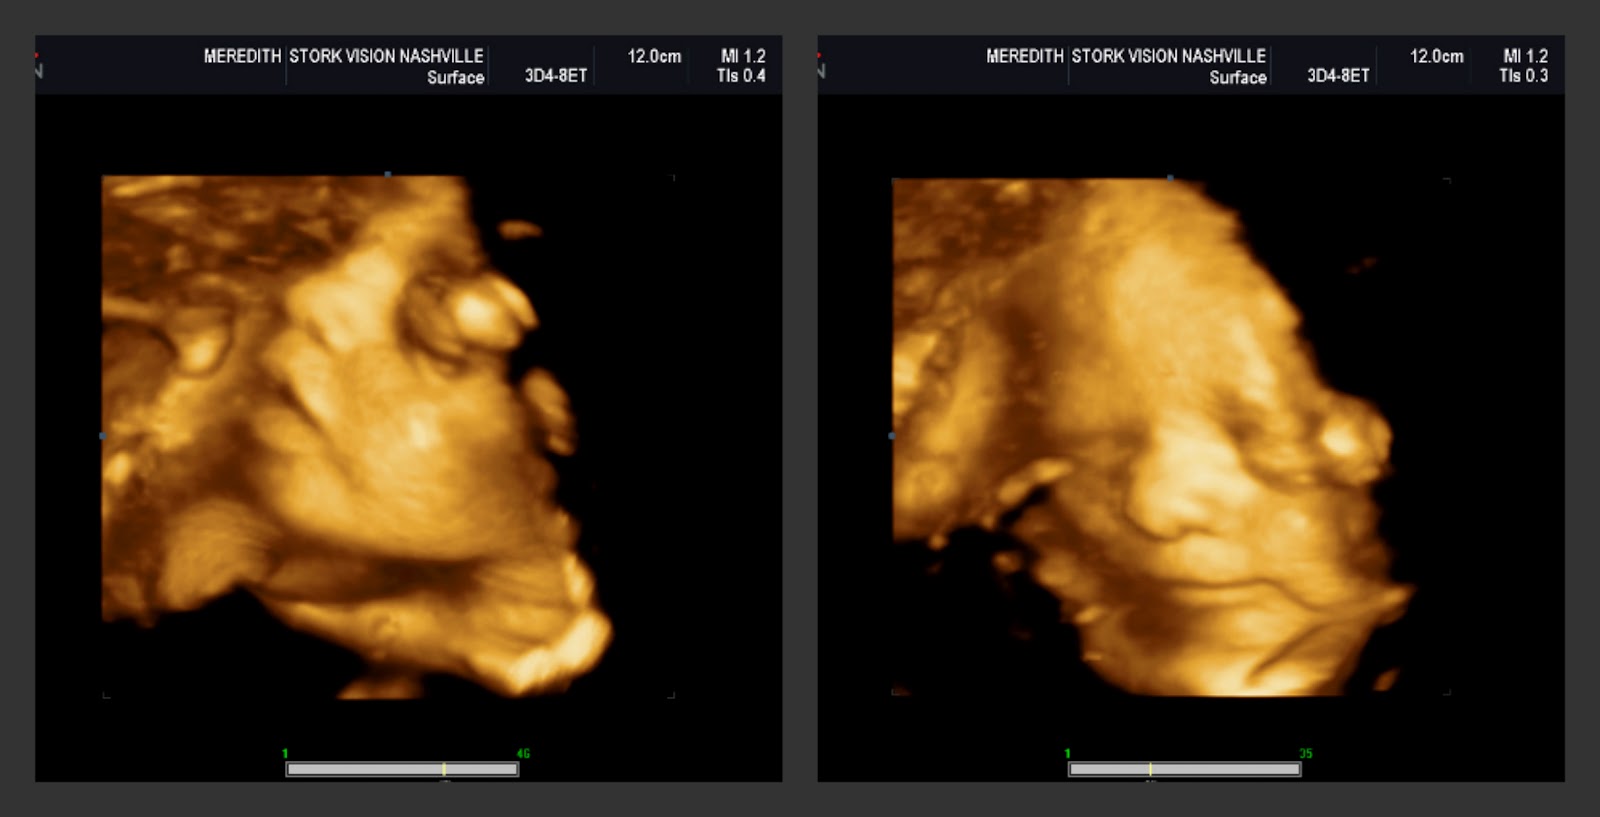

Best Moment this week: By far the best moment was the 3D ultrasound. Getting to see her facial features up close really makes it all seem that much more real. That there really is a REAL person in there with already distinct features and a personality. I'm so anxious to meet her!